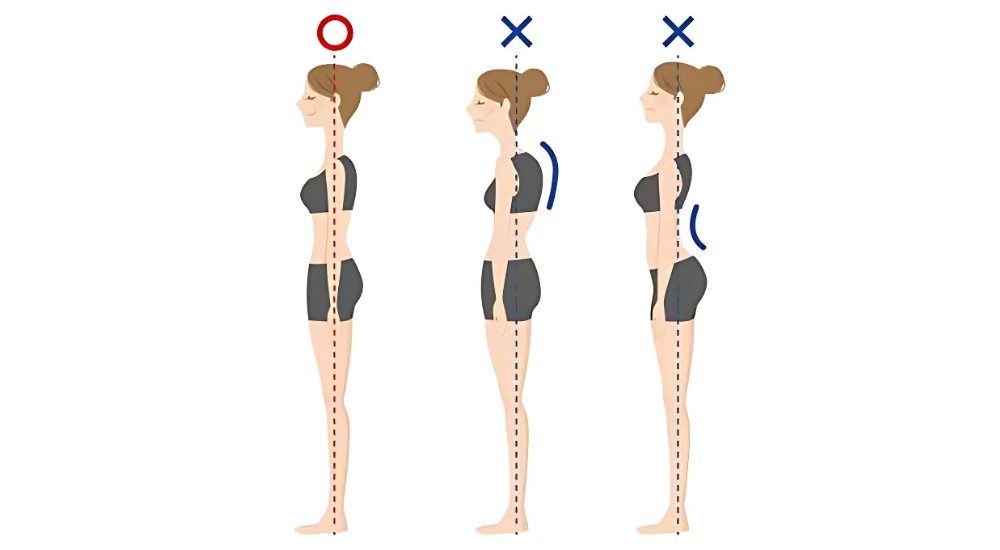

私たちの身体、特に背骨には、重力に対して効率よく身体を支え、衝撃を吸収するための自然なS字カーブがあります。

不良姿勢は、このS字カーブが崩れた状態であり、特定の部位に過剰な負担をかけてしまいます。

- 猫背: 背中の胸椎部分が過剰に丸まり、肩が前に突き出た状態です。

- 巻き肩: 肩関節が内側にねじれ、肩全体が前方に突き出た状態です。猫背に伴って起こりやすいです。

- ストレートネック: 本来ゆるやかに前にカーブしている首の骨(頸椎)が、まっすぐになってしまった状態です。猫背やうつむき姿勢が原因で起こりやすいです。